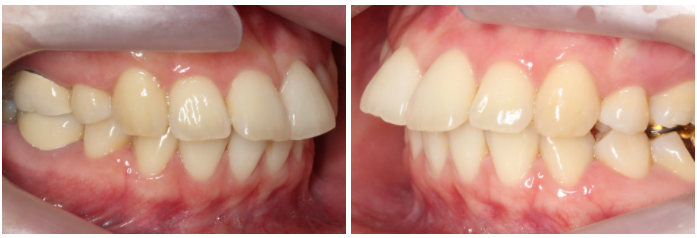

상악 클리피씨 교정 case

위의 case는 토끼앞니교정을

진행하기 전 정밀진단 상황으로

상악 중절치의 돌출감이

심한 모습인데요,

특히 upper teeth와

lower teeth의 정중선이

어긋나 있기 때문에

전치부의 crowding이

더 강조되는 상황입니다.

전치에서 구치까지 이어지는

협측 사진을 보시면 중절치의

튀어나온 모습을 명확하게

확인할 수 있습니다.